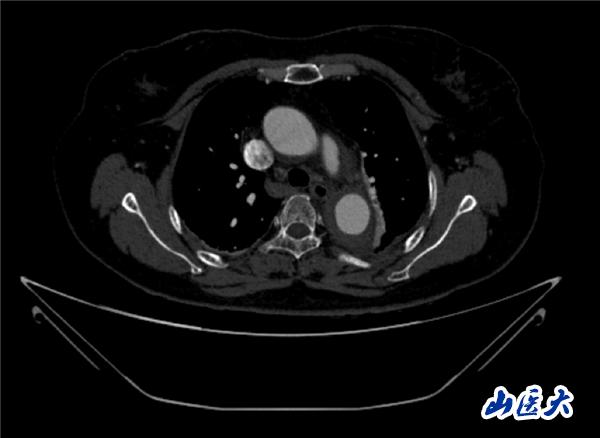

首例患者是一位55岁的女性,她患有高血压约2年时间,平时也会规律服用多种降压药,但血压控制始终不尽人意。2023年4月下午,她出现不明原因的头痛,在家拔罐缓解少许便未到医院就医,次日凌晨突感胸闷、胸背疼痛伴有呼吸困难等症状、家人急忙拨打了120,把患者送入医院急诊科进行救治,医生在急诊科行胸腹主动脉CTA时,显示主动脉弓部-降主动脉及腹主动脉壁间血肿,遂收治入医院血管外科,患者入院10天后复查血肿仍未有改善,依然伴有胸背部疼痛等不适,如不进一步处理,可能发展为夹层危及生命,患者及家属经过与医生团队了解沟通,决定进行创伤小、恢复快的介入手术治疗。张玮教授、符伟国教授、董红霖教授及其血管外科团队(闫盛、常文凯、田琴琴)共同商讨手术方案,最终确定使用Zipper™一体式主动脉弓覆膜支架系统,行胸主动脉覆膜支架腔内隔绝术+无名动脉、左颈总动脉、左锁骨下动脉分支重建术为患者进行治疗。董红霖教授及其血管外科团队根据患者术前头颅CT平扫提示双侧侧脑室旁缺血灶,血压控制不稳定,属夹层壁间血肿非典型夹层等风险点,制定了完整的手术方案,术中经股动脉置入Zipper支架主体,经预留导丝超选无名动脉,并确保主体支架对位准确,顺利置入左颈总动脉、左锁骨下动脉支架,重建弓上三分支。手术过程非常顺利。术后观察主动脉及分支覆膜支架定位准确;无内漏;分支支架通畅,动脉供血正常。

术中造影结果